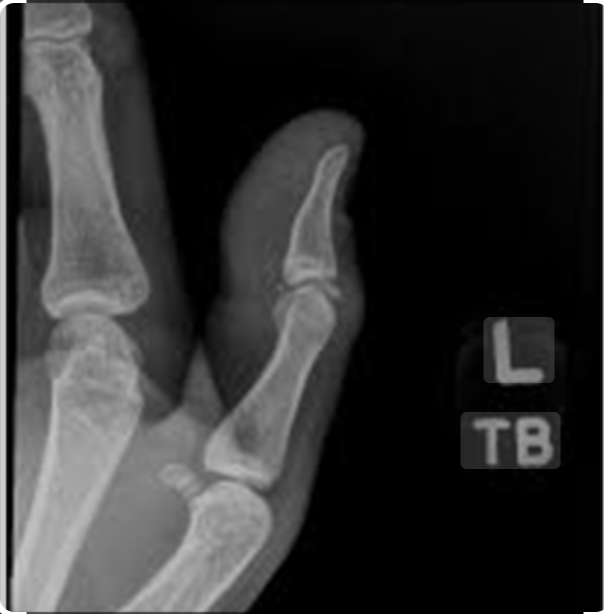

X-Ray Right Thumb (LAT) View

Medifyhome offers X-Ray Right Thumb (LAT) View at competitive prices. Radiography is a vital diagnostic tool in modern medicine, providing critical insights into the internal structures of the body. Medical imaging plays a significant role in diagnosing and treating musculoskeletal conditions. The X-ray of the right thumb in the lateral (LAT) view is an essential diagnostic tool that helps healthcare professionals evaluate bone and joint structures, identify injuries, and detect degenerative changes.

The lateral (LAT) view X-ray of the right thumb is a radiographic imaging technique used to evaluate the bones and joint structure of the thumb. It helps detect fractures, dislocations, arthritis, ligament injuries, and other abnormalities affecting the thumb joint. This imaging is commonly used to diagnose conditions such as fractures, osteoarthritis, ligament tears, and joint effusions.